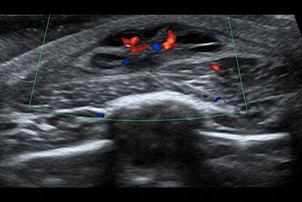

Texto alternativo para a imagem Créditos: Dra. Elazir Mota - Rio de Janeiro/RJ

Descrição das figuras: Formações císticas, com finos septos internos e vascularização periférica ao Doppler colorido, localizada na parede torácica esquerda, compatível com linfangioma.

• Ultrassonografia de partes moles: Trata-se do exame de imagem de escolha para avaliação de malformações vasculares e/ou linfáticas. No linfangioma macrocístico (forma mais comum), a lesão contém formações císticas, de tamanhos variados, com conteúdo líquido e separado por septos hiperecoicos. O interior dos cistos apresenta conteúdo anecoico, exceto quando há sangramento ou processo infeccioso associado, podendo o conteúdo do cisto tornar-se heterogêneo, com nível líquido-líquido. Ao Doppler colorido, a lesão mostra-se avascular (f iguras acima);